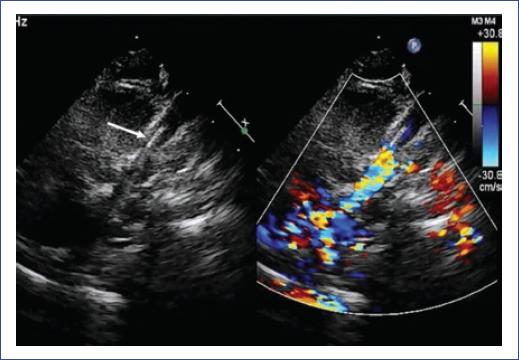

En las primeras 32 horas del postoperatorio, la paciente presentó evolución tórpida, con datos clínicos que mostraban la persistencia del síndrome de vena cava superior (SVCS). Esta sospecha se confirmó por ecocardiograma: obstrucción de VCS secundaria a nuevo trombo, el cual ocluía su luz dejando un diámetro de 1 mm, vena innominada con muy pobre flujo en su interior, atrio derecho con dos imágenes hiperecogénicas localizadas en el techo del atrio derecho y el piso del mismo, de 5.7 x 3.4 mm y 11.6 x 4.6 mm, respectivamente, movimiento septal paradójico y disincronía atrioventricular.

Los síntomas del paciente se resolvieron en las primeras 24-48 horas después de la colocación del stent. Por ecocardiografía, se confirmó la permeabilidad y ausencia de gradiente (Fig. 4). La paciente fue dada de alta con una evolución sin complicaciones.